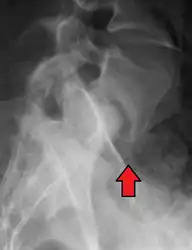

Retrolisthesis

Grade 1 retrolistheses of C3 on C4 and C4 on C5

A retrolisthesis is a posterior displacement of one vertebral body with respect to the subjacent vertebra to a degree less than a luxation (dislocation). Retrolistheses are most easily diagnosed on lateral x-ray views of the spine. Views, where care has been taken to expose for a true lateral view without any rotation, offer the best diagnostic quality.

Retrolistheses are found most prominently in the cervical and lumbar region, but can also be seen in the thoracic area.